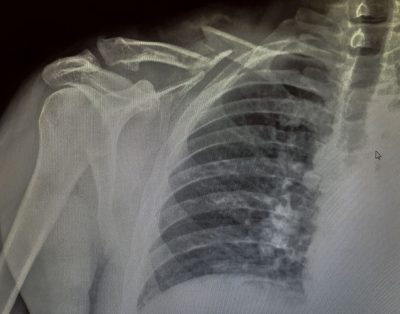

clavicle-xray